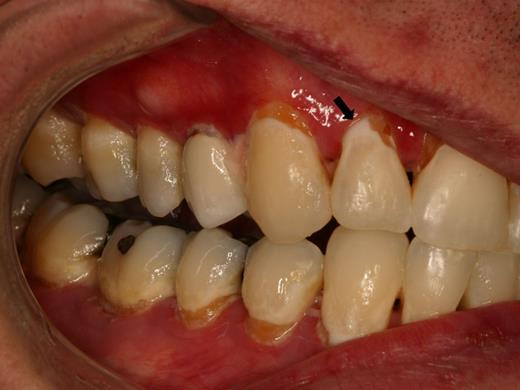

Rampant cervical dental caries affecting all of the teeth in a patient with cGVHD of the salivary glands. Demineralization changes (arrow) appear chalky white.

Dental caries

Patients with salivary gland cGVHD are at risk for developing secondary infectious complications because of diminished anticariogenic and antifungal activities. The development of accelerated and often rampant dental caries is a largely under-recognized complication of oral cGVHD that can develop rapidly, leading to extensive dental treatment, extraction of teeth, and significant social and economic costs.65-67 Before the development of frank carious lesions, the teeth may demonstrate demineralization changes along the cervical margins, characterized by a white and chalky appearance (Figure 7). Dental caries tend to develop at the cervical margins and interproximal surfaces where dental plaque accumulates because of lack of salivary flow. Exacerbating this problem is that patients with oral mucosal cGVHD may neglect oral hygiene because of discomfort associated with tooth brushing, compounding the effects of salivary gland changes. In addition to the effects on teeth, patients with salivary gland cGVHD are at significant risk for recurrent oral candidiasis, especially if there is ongoing topical corticosteroid therapy.

Prevention of dental caries is a critical component of salivary gland cGVHD management, and we initiate these measures in all patients with clinically significant disease (Table 4). Patients should be continuously reminded of the importance of maintaining a noncariogenic diet and good oral hygiene. In patients with severe salivary gland hypofunction, even when tooth brushing after eating is not feasible, patients should be instructed to rinse their mouths well with water. Prescription 1.1% sodium fluoride gel should be applied to the teeth nightly, either using a toothbrush to “paint on” to the teeth, or via custom-fitting trays that can be fabricated by the patient's dentist.68,69 In addition to topical fluoride, emerging evidence supports the use of a calcium/phosphate-based remineralizing agent (eg, GC MI Paste Plus, GC America), which can be applied just before topical fluoride.70,71 Dentists can place fluoride varnish twice annually during recall visits for further protection. Bitewing radiographs should be obtained on an annual basis to screen for interproximal decay (Figure 15), and areas of decay should be treated promptly and definitively (ie, the full extent of caries must be removed as risk for recurrent decay is high).